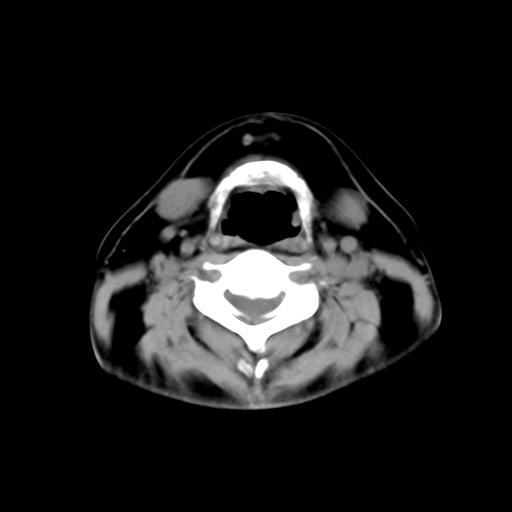

标题: CT24019:男,45岁,发现颈部肿物5个月。 [打印本页]

标题: CT24019:男,45岁,发现颈部肿物5个月。

男,45岁,发现颈部肿物5个月,彩超示:双侧颈部及下颌部软组织增厚。

考虑双侧颈项部良性对称性脂肪增多症。

双侧颈项部脂肪沉积